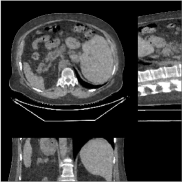

We reconstructed the abdomen volume from low-dose helical CT data. With an initialization of zeros, we ran the PWLS-EP algorithm with and for iterations with subsets for the mA and mA scans, respectively. For PWLS-ULTRA, we chose for the mA scan, for the mA scan, and ran it for outer iterations. The other parameter settings and the transform were the same as those used for the chest scan.

Fig.Β 10 shows the reconstructions (shown for the central axial, sagittal, and coronal planes in the 3D volume) for PWLS-EP and PWLS-ULTRA with patch-based weights () from low-dose abdomen scans. For the sagittal and coronal planes, we show the central out of axial slices. The supplement provides PWLS-EP reconstructions with different regularization strengths. The PWLS-ULTRA reconstructions in Fig.Β 10 have reduced noise as well as higher resolution, better structural details and shaper image edges than the PWLS-EP results. These results are further example of the potential performance of the proposed PWLS-ULTRA method in clinical settings.

Fig.Β 15 provides abdomen reconstructions (shown for the central axial, sagittal, and coronal planes) from low-dose (120kVp, 150mA and 35mA) helical CT data for PWLS-EP with different regularization strengths. We have labeled the reconstruction with good trade-off between image resolution and noise in bold for both doses. These images were used to initialize the PWLS-ULTRA reconstructions in Section IV.F.